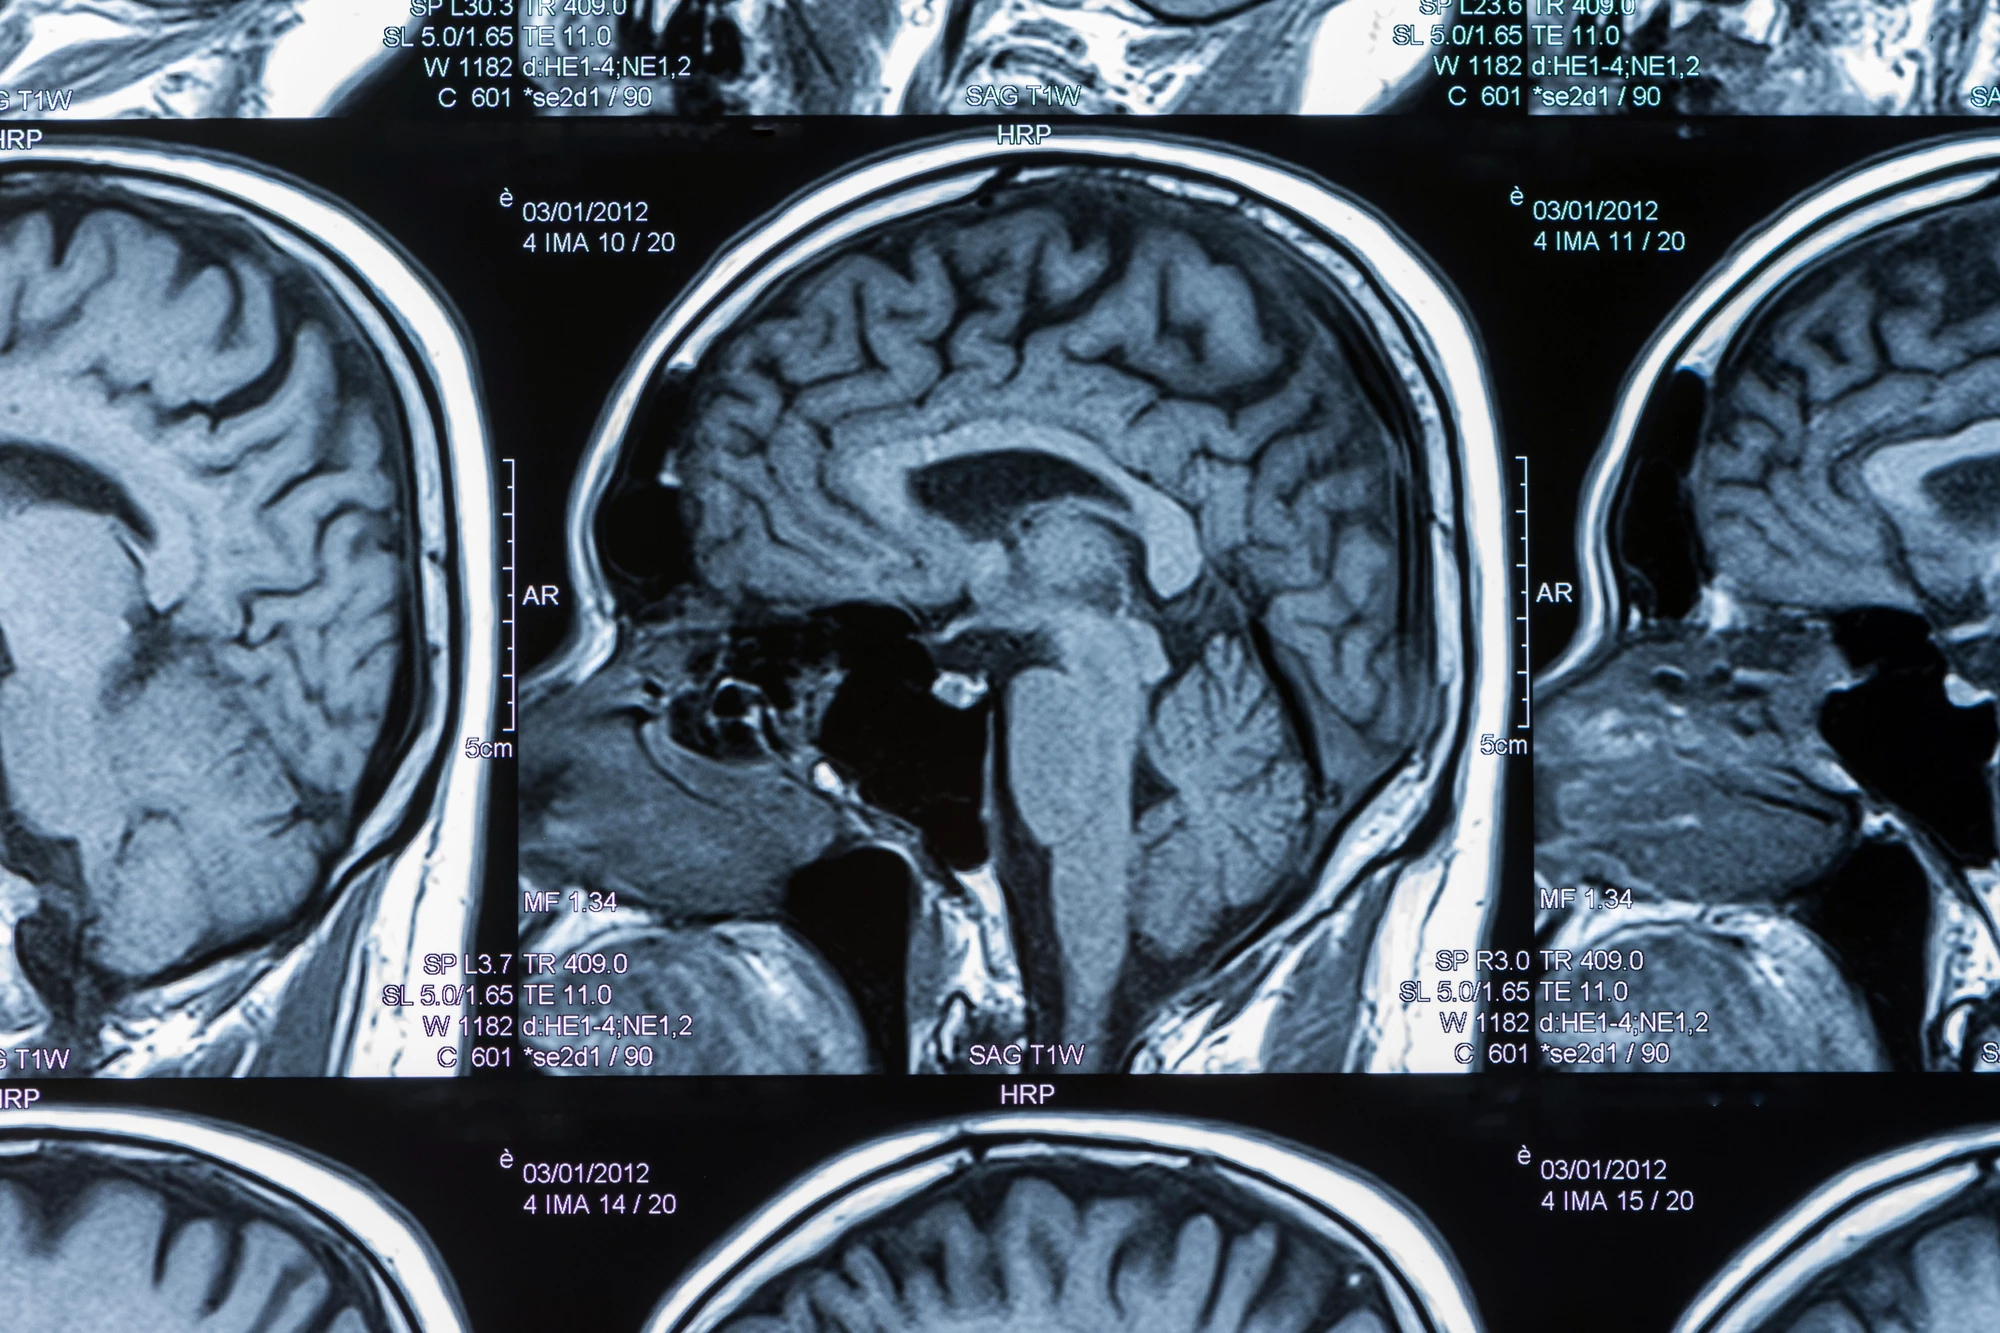

In a previous study, the researchers had shown that a single mild impact to the head, one that didn’t show up as structural brain damage on imaging such as an MRI scan, resulted in a temporary increase in brain swelling (edema) caused by the leakage of fluid and proteins from damaged blood vessels. This leakage disrupts the blood-brain barrier, a protective membrane that separates circulating blood from the brain tissue, leading to fluid build-up and increased pressure in the brain. The researchers noted that the edema from a single blow, which occurred in specific brain regions, peaked at six hours but resolved after a day.

For the current study, the researchers adopted a model that mimicked the types of sports-related head injuries that US National Football League (NFL) players might sustain. Nine-month-old female rats – roughly equivalent to a 27-year-old human – were divided into three experimental groups. One group was given a mild head injury each day for three consecutive days and injected with a 3 mg/kg dose of psilocybin after each impact. Another was given the same head impacts and injected with saline. The third, a control group, was given no head impacts and injected with saline. On day three, within an hour of receiving the last “bump on the head,” the rats had blood taken to test for biomarkers of mild head injury and underwent a brain MRI. Cognitive and motor behavior testing was carried out on days four to 10. A follow-up MRI was done on day 22.

“We impact them on the head,” Ferris said. “We don’t use anesthesia because people aren’t impacted under anesthesia [in real life]. Everything we do mimics the human experience. We’ve replicated the problem as true as we could to the actual experience. Our results we get with MRIs are the same results reported in the clinic. So not only does the experience replicate, but the results from that experience translate to the human condition as measured in scanners all over Boston.”